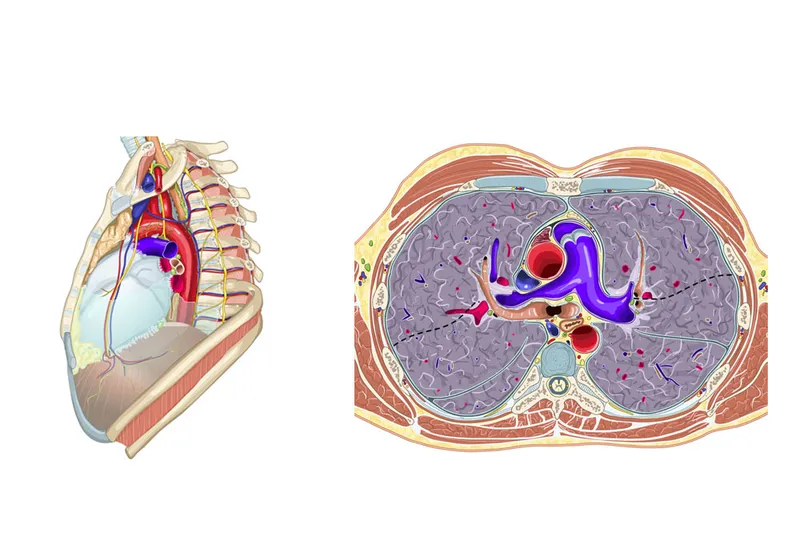

Diaphragmatic Hiatuses - The Great Escape

- Structures passing through the diaphragm at key vertebral levels.

- T8 (Caval Opening): Inferior Vena Cava (IVC), Right Phrenic nerve branches.

- T10 (Esophageal Hiatus): Esophagus, Vagus nerve (CN X).

- T12 (Aortic Hiatus): Aorta, Thoracic duct, Azygos vein.

β The esophageal hiatus is a common site for hiatal hernias, where abdominal contents (like the stomach) protrude into the thorax, potentially causing GERD.